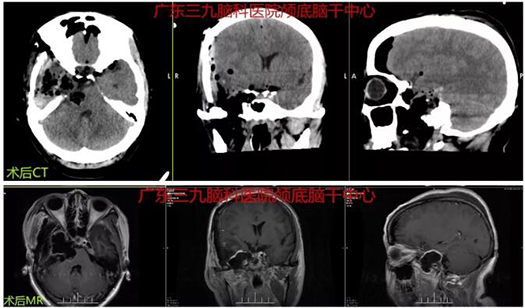

图3:术后CT及MR示右侧跨中后颅窝囊性占位性病变术后改变,原病灶已切除